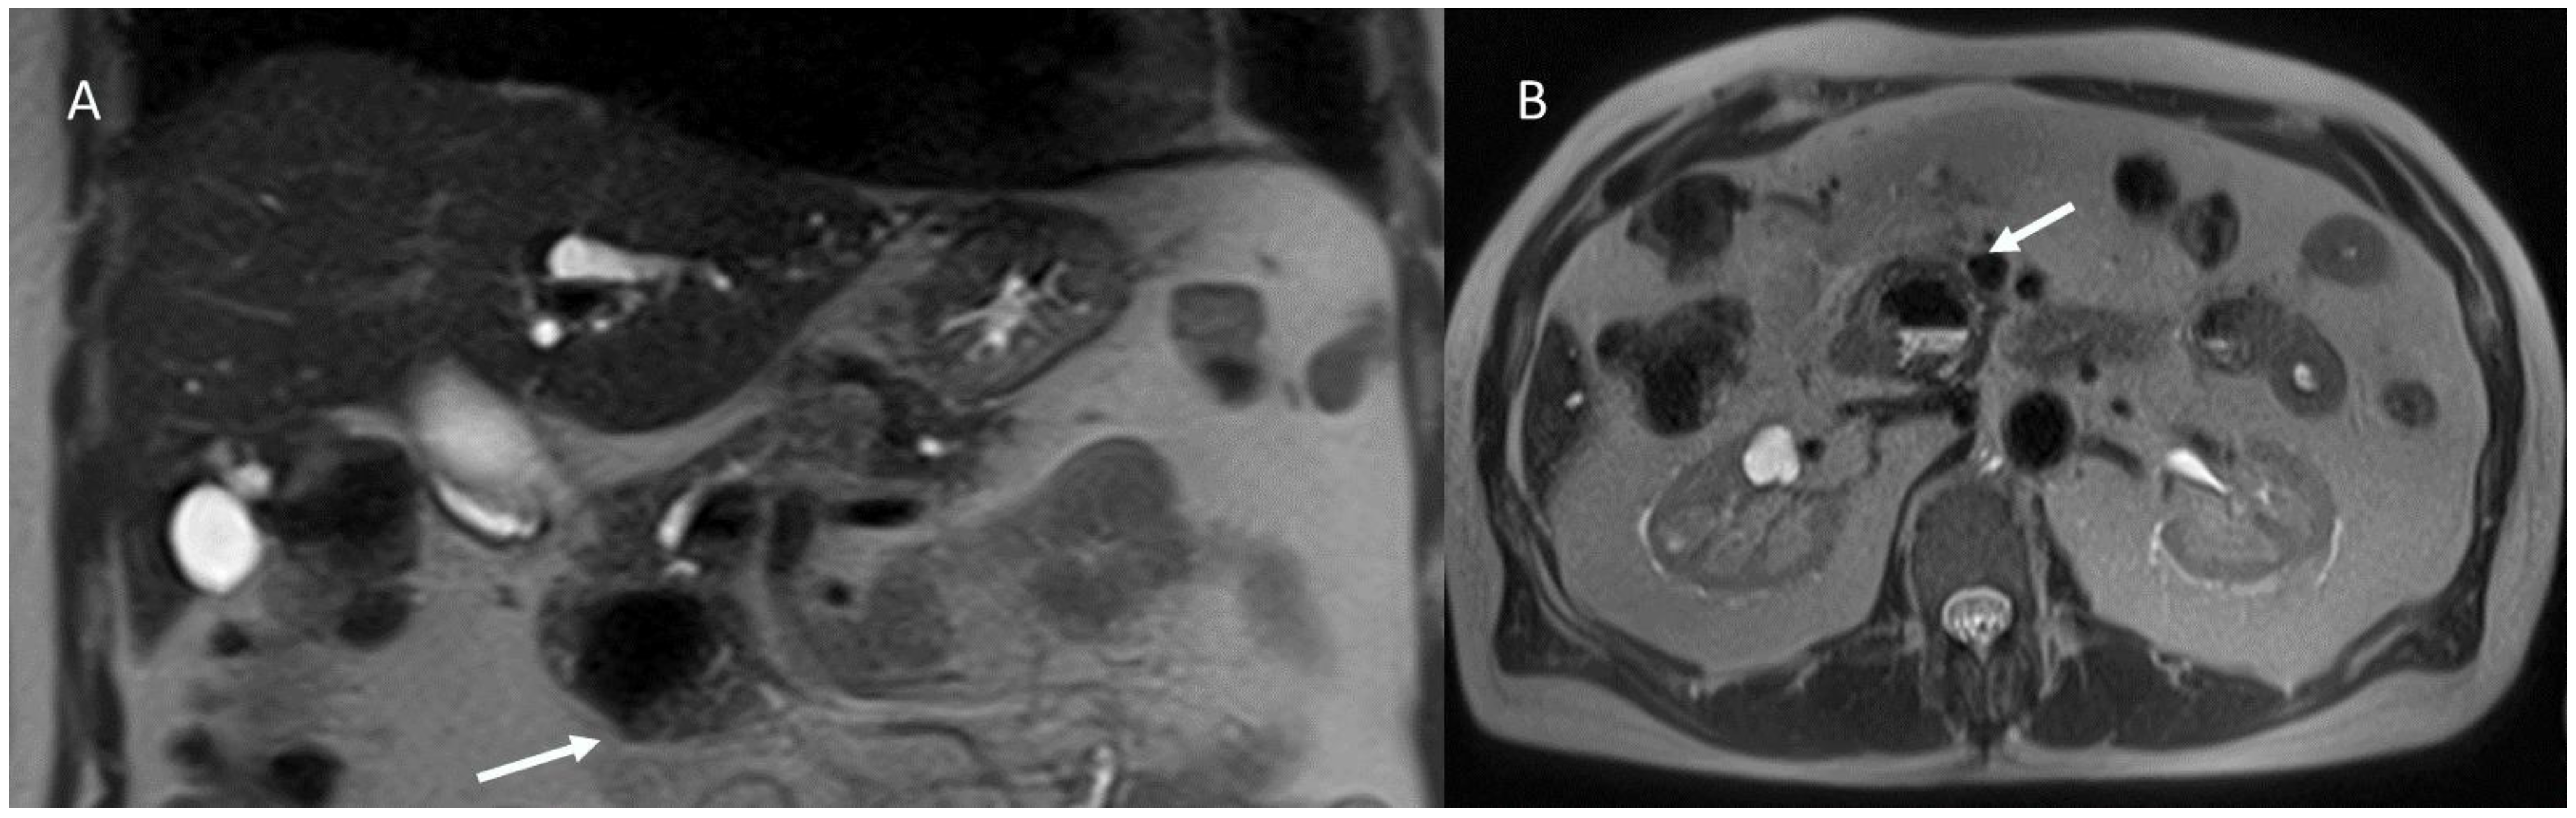

6.4. Hepatobiliary Mucinous Cystic Neoplasm

6.5. Diagnostic Management

- Granata, V.; Fusco, R.M.; Catalano, O.; Filice, S.; Avallone, A.; Piccirillo, M.; Leongito, M.; Palaia, R.; Grassi, R.; Izzo, F.; et al. Uncommon neoplasms of the biliary tract: Radiological findings. Br. J. Radiol. 2017, 90, 20160561. [Google Scholar] [CrossRef] [PubMed]